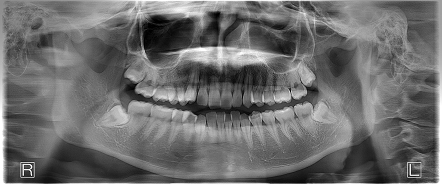

- 上の左右と下の左右に親知らずがあり、インビザラインの治療前に親知らずの抜歯を行ってから矯正を行なったケースです。

- 患者の症状

- 上の出っ歯は矯正治療前よりもひっこみ、前歯が全体的に整って綺麗な歯並びとなりました。